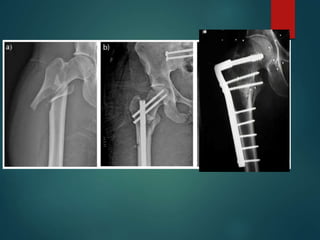

Intertrochanteric Hip Fx

 Treatment Options

 Stable: Dynamic Hip Screw (2-hole)

 Unstable/Reverse: IM Recon Nail

Subtrochanteric Femur Fx

 Classification

 Located from LT to 5cm

distal into shaft

 Intact Piriformis Fossa?

 Treatment

 IM Nail

 Cephalomedullary IM Nail

 ORIF